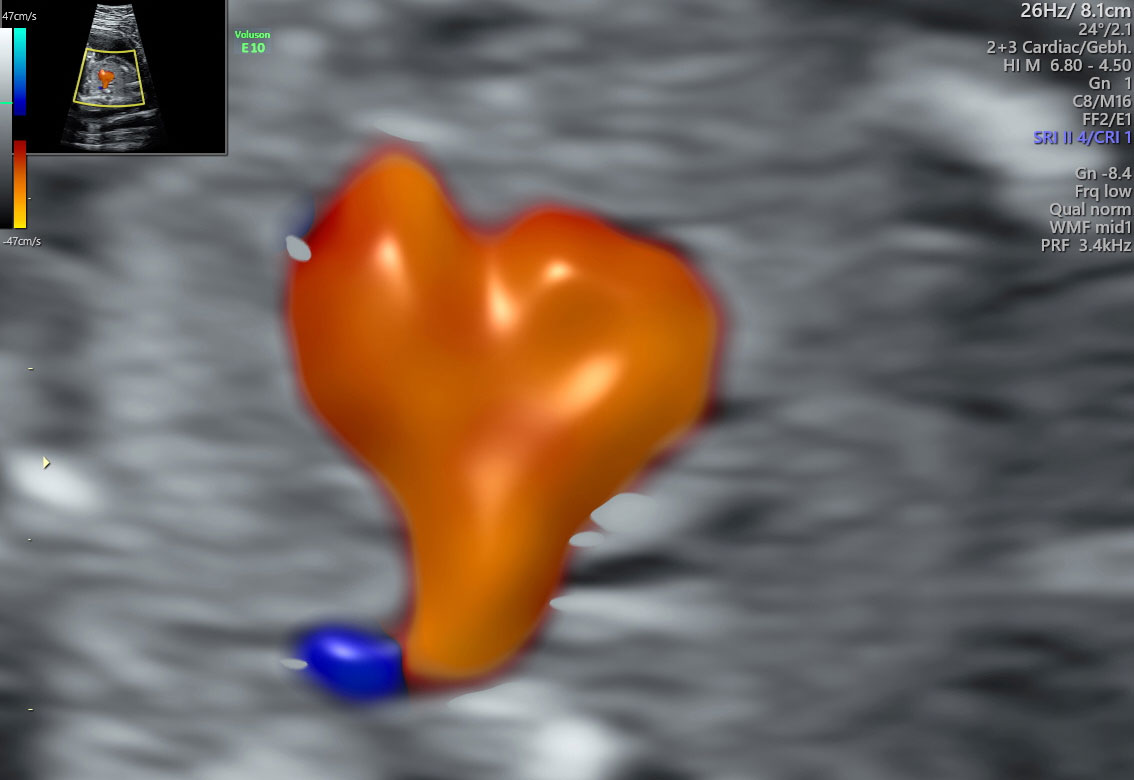

Bilder von Dr. U. Holtkamp

Fetale Herzechokardiographie

Durchgeführt von Dr. Holtkamp

Die sonographische Beurteilung des Herzens kann in Grundzügen auch bereits schon zu Zeiten der Nackentransparenzmessung erfolgen. Auch hier kommt die Matrix-Technologie zum Einsatz, weiterhin eine besondere Farbdopplertechnik, die sich radiance mode nennt.